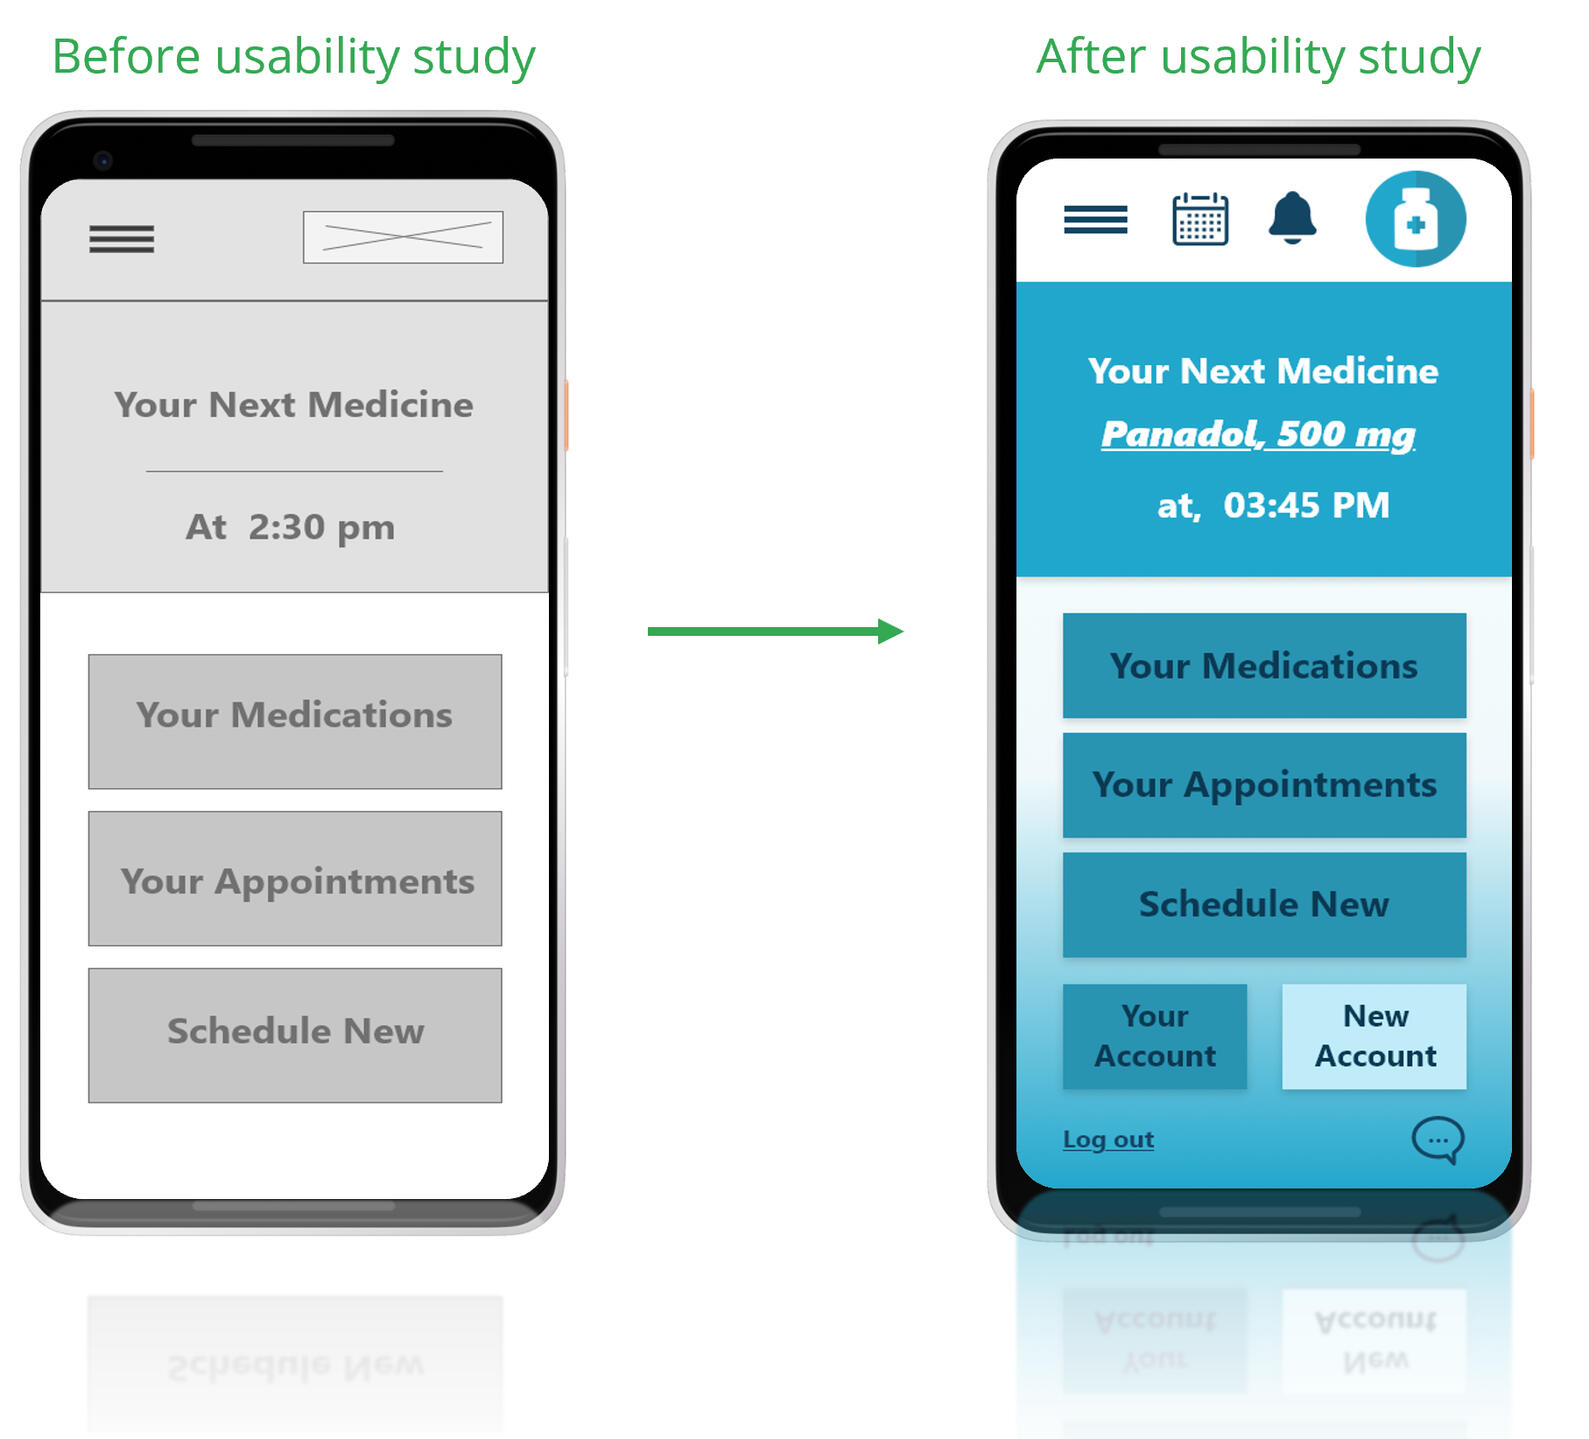

- HMW reduce confusion around dosages?Created Paper wireframes first, then low-fidelity Digital Wireframes on Adobe XD.

PrototypeDesigned low and high-fidelity prototypes using Adobe XD.Key Features:

TestUsability Study: FindingsA usability study was conducted to evaluate the functionality, accessibility, and overall user experience of the MediTracker prototype. Five participants were asked to perform common tasks such as signing up, setting medication reminders, and exploring app features.Key Findings:1. Security Matters

Users expressed the importance of securing their medical data. They appreciated having the option to log in with a username and password, which made them feel their personal health records were safe.2. Account Setup Needs Simplification

Some users found the account creation process slightly confusing or time-consuming. Clearer instructions and more intuitive input fields are needed to streamline onboarding.3. Desire for a Centralized Notification Area

Users liked having a dedicated notification space where they could view alerts about medications and doctor appointments. This feature helped them feel more organized and in control.MockupsBased on the insights gathered from the usability study, several key design improvements were implemented to enhance the user experience:- Notification Area:

A dedicated notification section was added, allowing users to easily view alerts for upcoming medications and doctor appointments. This helps users stay organized and ensures they don’t miss important tasks.- Login & Logout Functionality:

To address user concerns around data privacy and security, login and logout buttons were introduced. This ensures that personal health records are protected and only accessible to the user.These updates were reflected in the high-fidelity mockups for both mobile and desktop versions of the app.